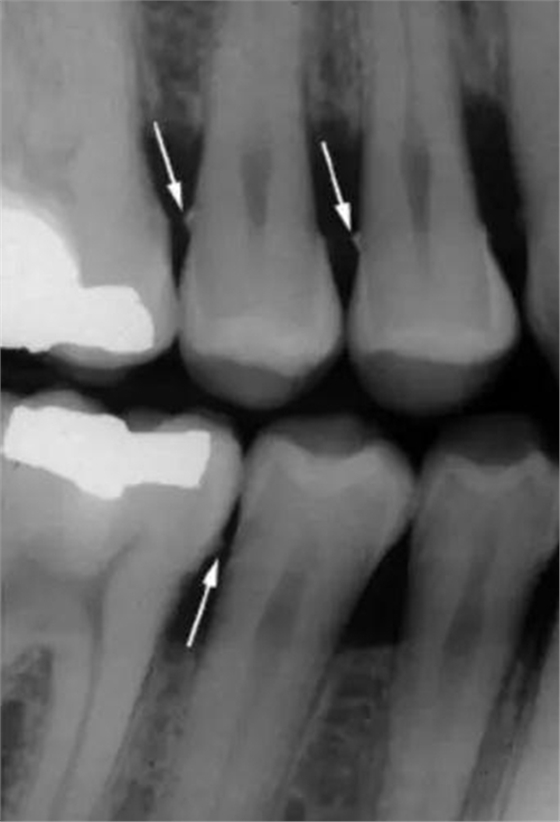

9. 根分叉入口:根分叉箭頭(高度特異性)

10. 磨牙牙根分離度 / 融合度

垂直咬翼片更適合牙周檢查。因?yàn)檠乐懿』颊咄ǔS泄俏眨绻諊?yán)重,水平咬翼片可能沒法顯示牙槽脊,而這時(shí)垂直咬翼片就顯示了其優(yōu)點(diǎn)。

另外,咬翼片在口腔里置放的位置所引起的圖像變形是最少的。當(dāng)然,它的不足之處是無法顯示根尖。所以,全口 X 光檢查包括根尖片和咬翼片,為的是取長補(bǔ)短。

圖 5 垂直咬翼片,清晰顯示牙槽脊位置(圖片取自 Carranza Clinical Periodontology 2012,第 11 版)